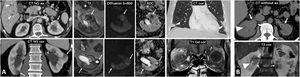

Clear cell renal cell carcinomas (ccRCC) with BAP1 somatic mutation. (A) Coronal CT in nephrographic phase. (B, C and D) Axial CT in corticomedullary phase. A 51-year-old woman with constitutional symptoms and a palpable left lumbar mass. CT shows a left renal tumour with highly infiltrative growth and heterogeneous enhancement (arrows), accompanied by a tumour thrombus in the left renal vein (hollow arrows), as well as pulmonary metastases (dashed arrows) and muscle metastases (arrowhead). Histological examination of the surgical specimen showed a histological grade 4 ccRCC with sarcomatoid features and BAP-1 somatic mutation.

PTEN syndrome-associated clear cell renal cell carcinoma (ccRCC). (A–D) PTEN syndrome. (A) Axial CT scan of the abdomen in the nephrographic phase. (B) Transverse section of ultrasound in B-mode of right hypochondrium. (C) Coronal cervical CT. (D) Photograph of the forehead. An 81-year-old male with haematuria. Physical examination revealed macrocephaly, a mass located at the base of the right side of the cervical region and evident papillomatous facial lesions (D). Imaging studies show several focal right renal lesions with intense enhancement and areas of necrosis (arrows). The largest of these is accompanied by a tumour thrombus, grade 4 in the Mayo clinic classification, which is echogenic and uptakes contrast (*). In addition, a large enhancing mass is visible near the right thyroid lobe (hollow arrows in C). A core needle biopsy was performed on the principal renal mass, which was diagnosed as ccRCC, and on the thyroid mass, which was diagnosed as follicular thyroid cancer, the most frequent histological subtype in this syndrome. The patient died before genetic testing was carried out, but they met the criteria for PTEN syndrome. (E) PTEN syndrome simulator. Coronal CT in nephrographic phase. A 79-year-old female. Lobulated renal mass with intense enhancement and central necrosis (arrows) together with a similar mass near the left thyroid lobe. While PTEN syndrome was suspected, the histological diagnosis was ccRCC with thyroid metastasis. The patient did not meet any other clinical criteria for PTEN.

Hereditary leiomyomatosis and renal cell carcinoma. A 26-year-old female with constitutional symptoms, pain and a palpable mass in the left lumbar region. (A) MRI. Axial images with T1-weighted, T2-weighted, and parametric map of apparent diffusion coefficient. (B) Coronal non-contrast CT, nephrographic phase and excretory phase. Infiltrating mass measuring 135 mm in the left kidney (arrows). There are extensive cystic-necrotic and haemorrhagic areas (*), the latter with high T1 signal and water diffusion restriction, as well as papillary projections with subtle enhancement on CT, with an increase of between 23 and 31 HU in the nephrographic phase (arrowheads). It is accompanied by a tumour thrombus in the left renal vein, with similar characteristics. (C) Sagittal T2-weighted pelvic MRI performed three years earlier. Uterus with multiple hypointense fibroids (m). (D) Coronal CT image in the nephrographic phase one year after nephrectomy. Recurrence in the form of a heterogeneous mass in the surgical site (r) and liver metastases (dashed arrows). The nephrectomy specimen was initially diagnosed as papillary renal cell carcinoma type 2. Later, loss of FH staining was observed in a controlled immunohistochemical study, allowing for the diagnosis of this specific entity.

Birt-Hogg-Dubé syndrome. A 68-year-old male. Incidental finding in an ultrasound examination. (A) Ultrasound centred on a lesion. In B-mode (arrow) it is discreetly hypoechogenic, with contrast enhancement (red ROI), purely intravascular, almost as intense as that of the renal parenchyma (yellow ROI), both in the static image and in the time-intensity curve (not shown). Core needle biopsy was performed on this lesion and on another lesion (not shown), with histological diagnoses of a chromophobe cell renal carcinoma and an oncocytic lesion. (B) CT Multiple focal bilateral renal lesions of various sizes and well demarcated (at least six were identified) with moderate enhancement, somewhat weaker than that of the renal parenchyma and more intense in the corticomedullary phase (arrows). One had some small focal calcification (not shown). Thin-walled cysts are also visible at the lung bases (arrowheads). (C) MRI centred on the larger lesion (arrows). It shows signal intensity in T1 (similar for in-phase and opposed-phase sequences) and T2, as well as moderate water diffusion restriction, with an average ADC value of 0.91 × 10−3 mm2/s and clearly less intense enhancement than that of the renal parenchyma in the time-intensity curve (ROI and red and yellow curves, respectively). The genetic study confirmed a germline mutation of the FLCN gene in heterozygosis.

Tuberous Sclerosis Complex in a 45-year-old female. CT. Innumerable bilateral renal angiomyolipomas with gross fat. Its exophytic growth is noteworthy due to the risk of bleeding associated with its size and the abundance of aberrant vessels, one of which is in the lower pole of the left kidney (arrow). Hepatic angiomyolipomas are also visible (double arrow), along with sclerotic lesions in the axial skeleton (arrowheads), small subependymal calcified lesions (hollow arrows) and multiple thin-walled cystic lesions in both lungs (dashed arrow) in the context of pulmonary lymphangioleiomyomatosis.

Lynch syndrome in a 73-year-old male who previously underwent surgery for sigmoid colon adenocarcinoma. Haematuria. CT. Mass affecting renal pelvis (arrowhead) and infiltrating renal parenchyma (arrows) with scant enhancement. It corresponded to a urothelial carcinoma accompanied by enlarged retroperitoneal lymph nodes (*) and a synchronous bladder lesion (dashed arrow). See part of the mechanical colorectal anastomosis (hollow arrow).

Renal metastases and mimics. (A) Renal metastases of squamous-cell carcinoma of the lung (arrow), exhibiting multiple renal masses with poor enhancement and infiltrative behaviour (*). (B) Renal metastases of adenocarcinoma of the gallbladder with extensive infiltration of the adjacent liver parenchyma (arrows) and extensive peritoneal carcinomatosis, also within an inguinal hernia (hollow arrows). The renal lesions (*) behave similarly to the primary neoplasm, with moderately intense and heterogeneous enhancement, and abundant tumour necrosis. In this case, the lesions have a more expansive behaviour. (C) Clear cell renal cell carcinoma mimicking breast carcinoma metastasis in a 64-year-old woman undergoing oncological follow-up due to her medical history. Exophytic, expansive renal cortical lesion with enhancement almost as intense as that of the parenchyma (arrows). A retrospective review of previous studies showed that it was present in a study performed two years earlier (dashed arrow), with slower growth than expected for metastasis. The diagnosis was confirmed following percutaneous biopsy and tumour removal. (D) Contralateral renal metastases of clear cell carcinoma (ccRCC) or Von Hippel-Lindau? An 82-year-old female underwent a right nephrectomy for ccRCC. CT images show numerous markedly enhancing contralateral renal nodules with cystic appearance and thick walls, which is the usual appearance of lesions in Von Hippel-Lindau syndrome. However, hypervascular metastases coexisted in both the left adrenal region (arrowhead) and lung (not shown). The patient died without a confirmatory genetic diagnosis.

Renal lymphoma. (A) Diffuse infiltration of both kidneys (arrows), in addition to infiltration also demonstrated by a lymphoma of the prostate (+), with the stem of a bladder catheter in its urethral section, and a lymphoma of the gastric wall (*). (B) Multiple and bilateral nodules with discrete enhancement (*). (C) Perirenal solid masses (*) with discrete enhancement, which infiltrate the superficial renal parenchyma (arrows) and penetrate the renal sinus (+), causing discrete hydronephrosis (arrowheads), albeit sparing the vessels (not shown). (D) Peripelvic and renal sinus infiltration (*), in this case accompanied by abundant retroperitoneal and mesenteric lymphadenopathies (+). (E) Infiltration of the renal sinus, with significant water diffusion restriction, high signal in the diffusion sequence with B = 800 s/m2 and low signal in the apparent diffusion coefficient (ADC) map (arrows).